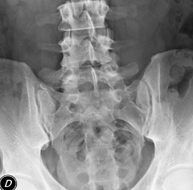

- RX Abdomen

Tècnica que usa els raigs X a través de la qual s'obtenen imatges de l'abdomen (estómac, intestí prim, intestí gros, fetge, ronyons, bufeta, pelvis òssia, etc.) per al seu estudi. - RX Columna lumbar

Procediment que permet, mitjançant l'ús de raigs X, i després d'injectar un contrast a l'interior de l'articulació, detectar lesions d'aquestes articulacions (cartílag, os, tendons, etc. ) segons la distribució del contrast. - RX Pelvis

Procediment que usa els raigs X a través de la qual s'obtenen imatges de la pelvis per al seu estudi, especialment dels ossos pèlvics. - RX Edat òssia